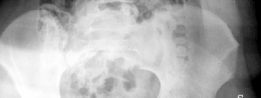

Revision THA Acetabulum Paprosky Type IIIA. ARMD with Metallosis with Severe Periacetabular Osteolysis and Co…

Case Title: Acetabular Impaction Grafting Demographics Age: 78 Sex: female BMI: 28 Relevant Past Medical Hist…